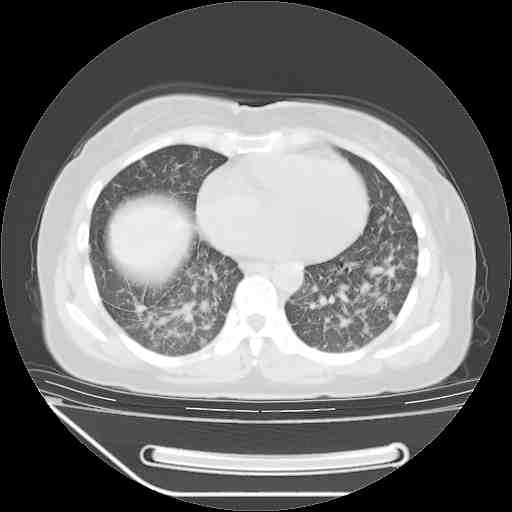

下面是今天刚刚做的,在上海治疗,吃了家属也说不清的一种药,一个月1万左右,

考虑  腺癌肺内转移,治疗较前病灶缩小、减少

支持肺癌并肺内淋巴管炎,  原发灶小了,但转移较前片明显了.

支持右肺下叶周围型肺癌并肺内淋巴管炎,  原发灶小了,但转移较前片明显了.。

支持右肺下叶周围型肺癌并肺内淋巴管炎;病灶有所控制。

支持右肺下叶周围型肺癌并肺内淋巴管炎,  原发灶小了,但转移较前片明显了.